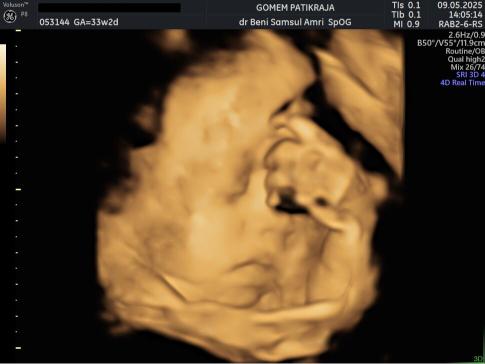

Gambaran Hasil USG Janin 33 Minggu

Jadwal USG

Jadwalkan pemeriksaan USG rutin untuk melihat perkembangan organ janin dan detak jantungnya. Visualisasi janin akan membantu Anda merasa lebih tenang dan terkoneksi dengan bayi.